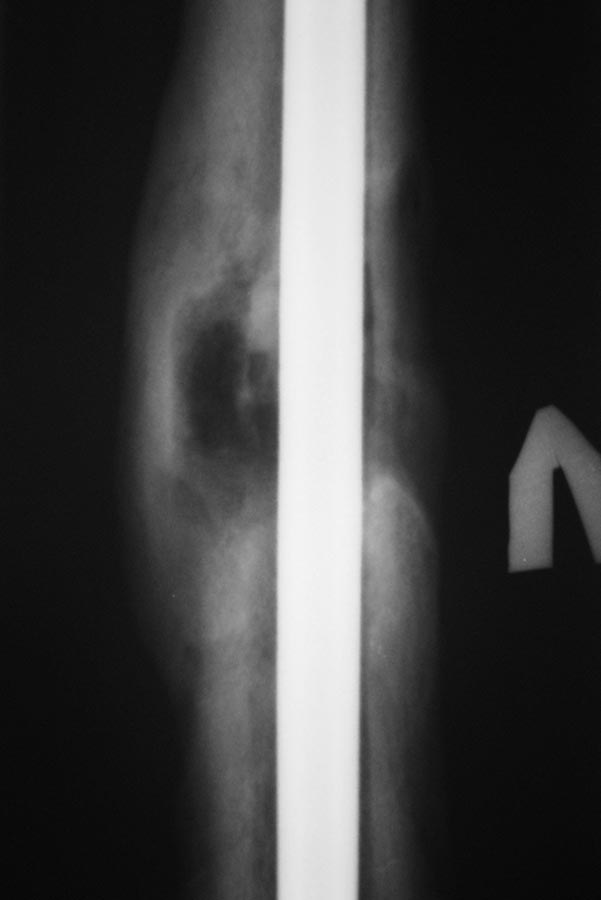

Спустя еще 4-5 мес обратился с жалобами на припухлость в области дистального блокирования. В поликлинике сделали снимки и, с подозрением на остеомиелит, оправили в стационар.

Сегодня: местно - без признаков инфекции. В области дистального блокирования припухлость плотно-эластичной консистенции. При пункции получить ничего не удалось. Лейкоциты 6,0; СОЭ - 22. СРБ-18. Температура в вечерние часы 37-37,2

Снимки представлены.